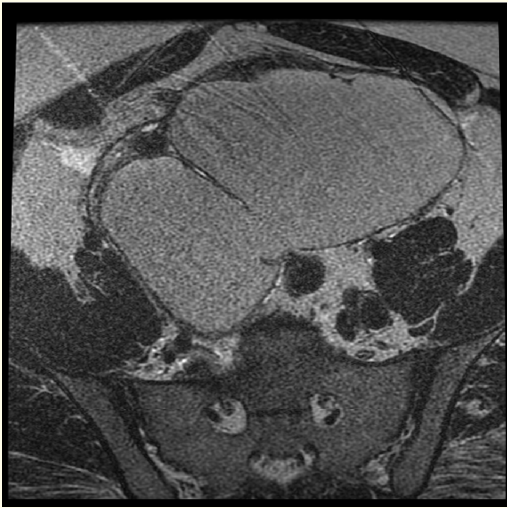

Laparoscopic Excision of a Huge Ovarian Endometrioma-A Case Report

Amos A Akinbiyi and Amber Sucharov. 11(11): 20-24.